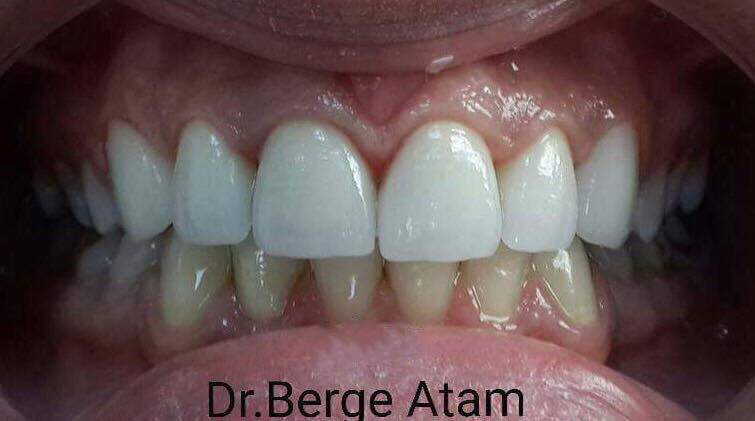

Restoration of anterior teeth with virors based on zirconium oxide

For the front teeth of the young patient, vinirs E-max based on zirconium oxide, on the canines – veneers E-max, and one press crown on the mandibular incisor were made.